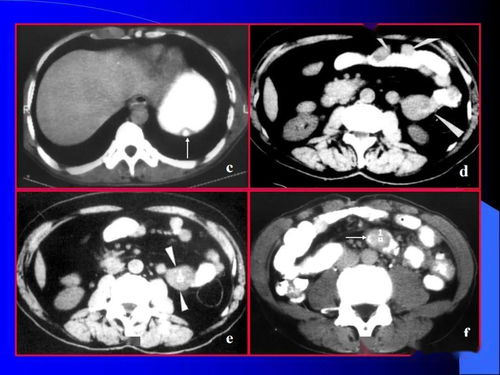

对于腹腔肿瘤的诊断,影像学检查是一种重要的手段。彩超适用于筛查肝、胆、胰、肾等实质性脏器肿瘤。而CT/MRI的高分辨率可以发现深部或小肿瘤,增强CT对于判断肿瘤分期和浸润范围尤为重要。PET-CT则用于原发灶不明或转移灶的排查。针对不同类型的肿瘤,也有特定的肿瘤标志物检测,如胃肠道肿瘤的CEA、CA199、CA724等。